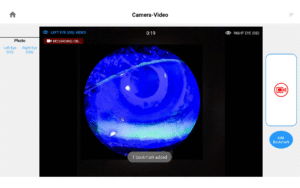

Photos & Videos. Clinical Documentation. Patient Education. Reimbursement.

Illuminate your exams and transform patient engagement like never before. When patients see detailed images of their eyes, they gain a deeper understanding of their health and recognize the importance of compliance and follow-up care. Throughout development, our team saw firsthand the profound impact of imaging in the clinic—watching patients smile, express genuine appreciation, and embrace their health journey. That unforgettable experience remains the most rewarding part of our work.

Opteon was born and developed in the clinic, meticulously tested, and perfected through countless hours to ensure that it flows with your exam routine — delivering unmatched reliability and efficiency.